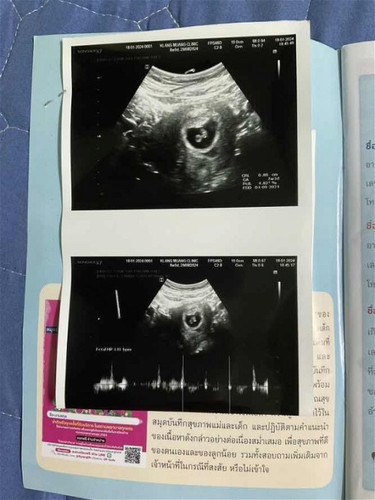

แม่บ้านนี้ไปตรวจการตั้งครรภ์ 6w+1d เจอถุงการตั้งครรภ์แต่ยังไม่เจอตัวน้องหมอนัดติดตามวันนี้ครบ 8w พอดีค่ะเจอน้องแล้วได้ยินเสียงหัวใจน้องแล้วค่ะ แม่ๆทำใจให้สบายๆนะคะไม่เครียด หากแม่ไม่มีอาการเลือดออกใดๆ แม่บ้านนี้หมอนัดอีกที่นู้นเลยค่ะอีก 1เดือน 12w เลยหมอบอกว่าอาจจะได้ทราบเพศเลยค่ะ ขอให้แม่แข็งแรงทั้งแม่ทั้งน้องเลยนะคะ

ขอบคุณค่ะแม่ ของบ้านแม่เป็นอย่างไรบ้างนะ ผ่านมาแล้วตั้ง 3ท้องเท่ากับ 0คน รอบนี้ขอให้ฟ้าใจดีกับเราบ้างค่ะและแล้วฟ้าก็ใจดีกับเราค่ะเห็นน้องแล้วรอบหน้าหมอนัดอีก 1เดือนจะได้ลุ้นเพศน้องแล้วค่ะแม่ตื่นเต้นมากไม่เคยมีโมเม้นแบบนี้เลยค่ะ ตอนซาวด์นี้แม่ลุ้นสุดๆค่ะสุดท้ายเจ้าตัวน้อยก็มาให้เราเห็นค่ะดีใจน้ำตาไหลไม่รู้ตัวเลยค่ะ